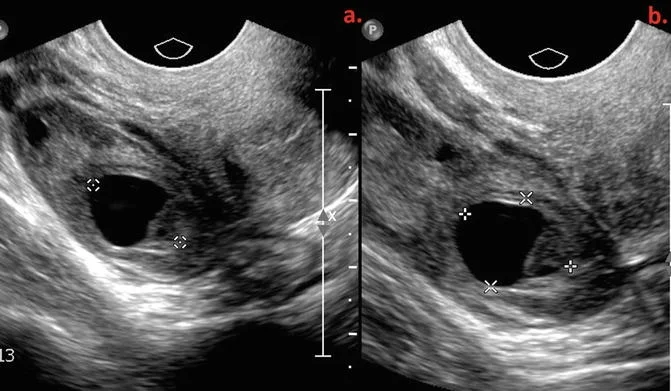

• Xoắn buồng trứng trong thai kỳ (Ovarian Torsion in Pregnancy).

• Nang buồng trứng thai nhi (Ovarian Cyst)